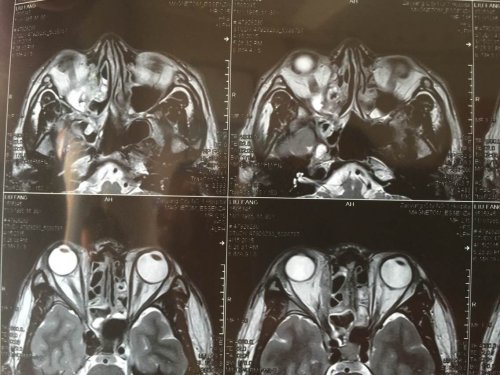

昨日(2015—04—15)MR影像报告:

03—27 影像图:

04—15 影像图

03—27 影像图:

04—15 影像图